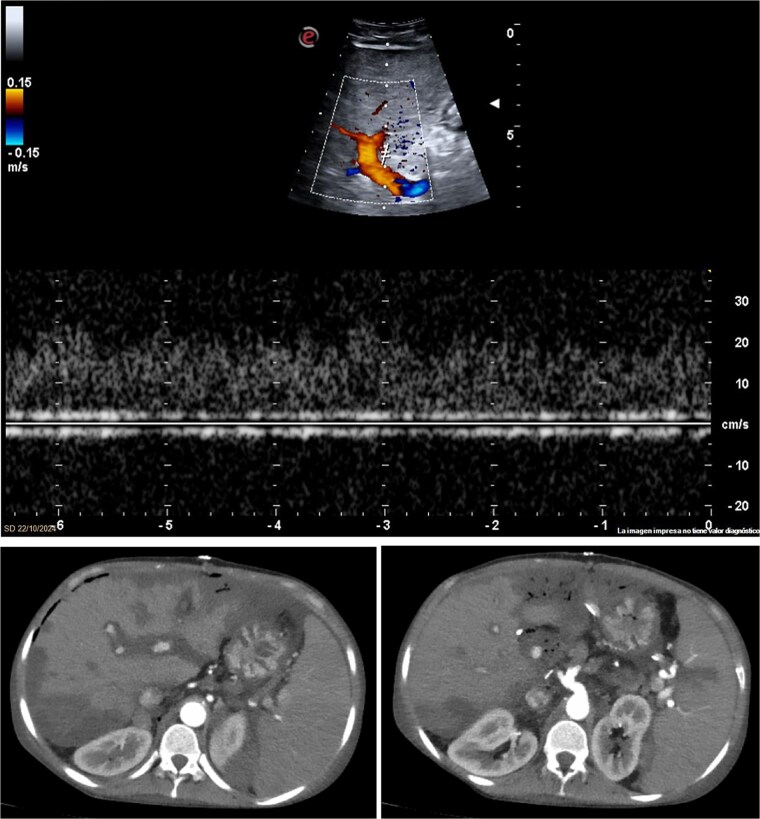

Liver retransplantation is a technically demanding procedure, particularly in patients with complex surgical histories and vascular complications such as hepatic artery thrombosis (HAT). We report the case of a 25-year-old woman who underwent a third liver transplant for graft cirrhosis. The procedure was technically demanding due to multiple adhesions, porta hepatic fibrosis, portal hypertension, and hypoplastic vasculature. Arterial reconstruction used an end-to-side anastomosis between the donor's celiac trunk and the recipient's splenic artery. On postoperative day 3, she underwent acute HAT and needed an urgent retransplantation (fourth liver). A new arterial anastomosis was created between the origin of the splenic artery and a Carrel patch from the donor's celiac trunk. The patient made a full recovery. This case highlights the technical challenges of liver retransplantation and the importance of individualized vascular strategies.